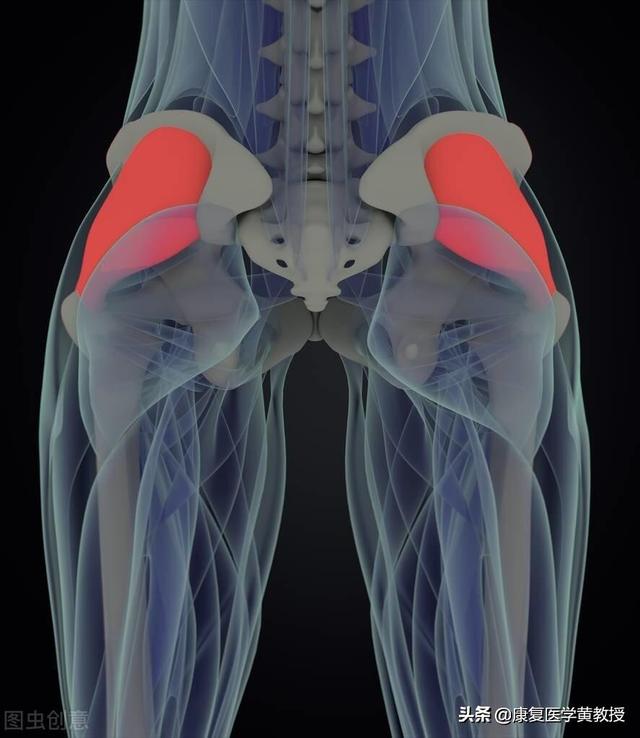

Aucune des opérations du système musculo-squelettique (y compris la colonne cervicale) ne peut se faire seule, et lorsque nous voulons activer un mouvement articulaire, nous devonsLe système nerveux central, le système nerveux périphérique, le système myofascial-squelettique, le système sensoriel-récepteur et le système cardiovasculaire fonctionnent ensemble.Pour effectuer une simple rotation ou un hochement de tête, l'exécution du mouvement est affectée par des problèmes dans l'un ou l'autre des sous-systèmes du système.

La colonne cervicale veut bouger et ce sont les muscles qui s'en chargent.

À l'origine, les muscles étaient indépendants les uns des autres, chacun exerçant une force dans sa propre direction.

Mais en cas de mauvaise posture prolongée et de force toujours exercée dans une direction, les muscles de cette direction sont toujours comprimés et, avec le temps, des adhérences peuvent se produire.

Plus ils s'agglutinent, plus la force est grande, plus ils tirent sur la colonne cervicale. Plus la colonne cervicale est déformée, plus les muscles sont amenés à se serrer les uns contre les autres. Un cercle vicieux !

Le principe de la mini-aiguille est simple : elle détache et sépare les tissus adhérents, réduit la traction musculaire sur la colonne cervicale et soulage la pression sur les tissus adjacents de la colonne cervicale.